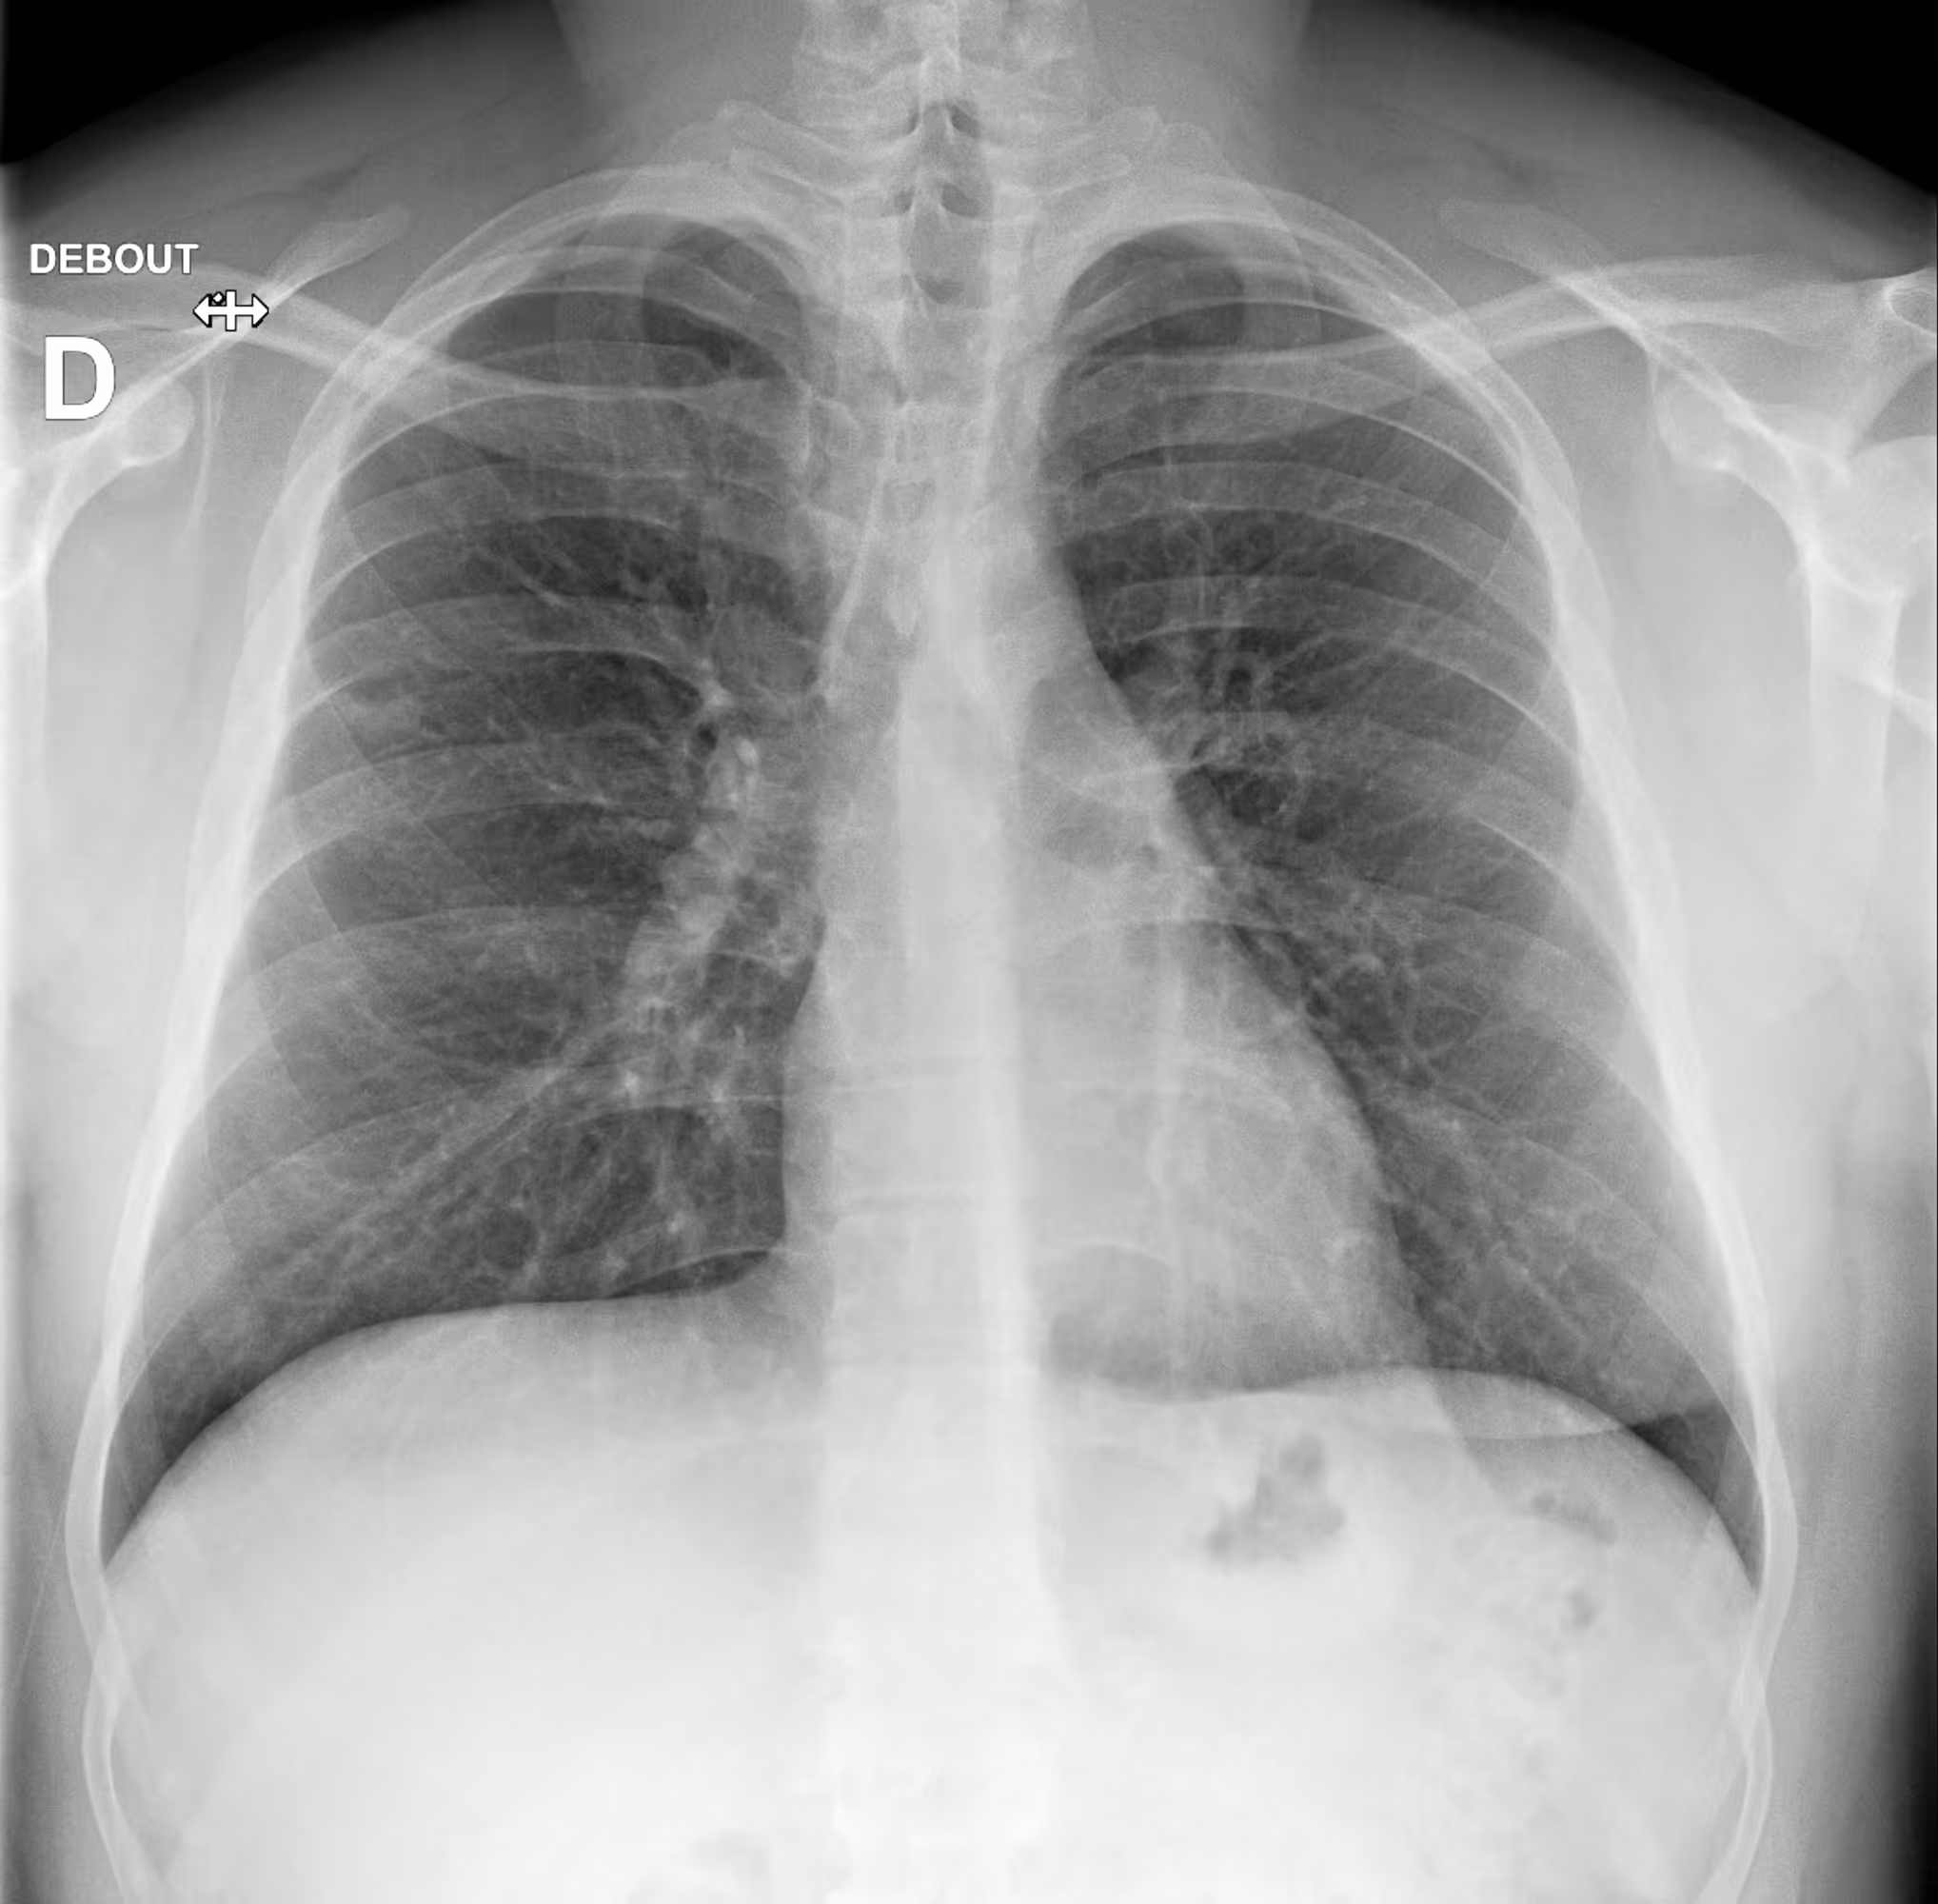

Indication

A 54-year-old male with respiratory difficulty.

Results

ChestView detected an infectious region in the right lower lobe and incidentally identified left hilar lymphadenopathy